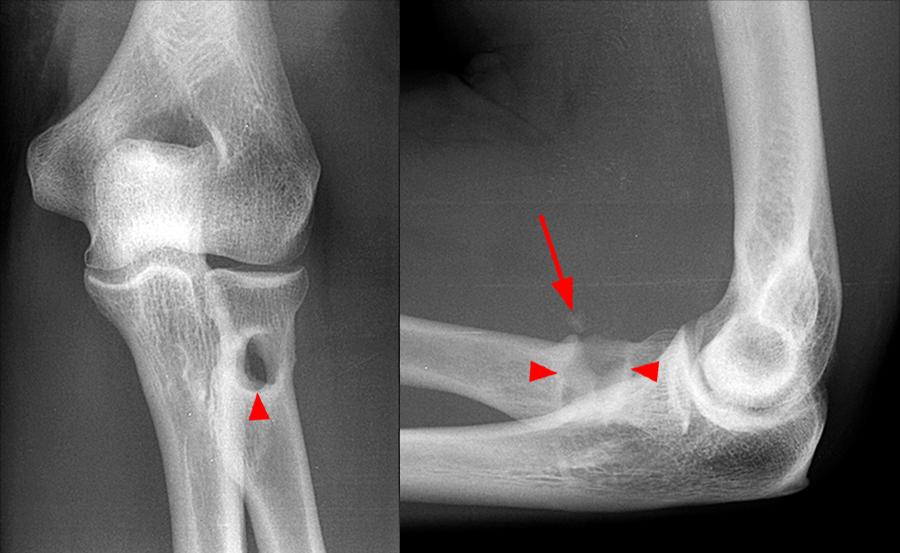

From dontforgetthebubbles.com

Elbow XRays Elbow Tendonitis Xray These give detailed images of your elbow joint and can help to find. It is positive if testing generates paraesthesia without pain. It usually goes away with rest but can sometimes last over a year. Tennis elbow is a condition that causes pain around the outside of the elbow. Specifically, doctors look for tenderness in very specific sites on the. Elbow Tendonitis Xray.